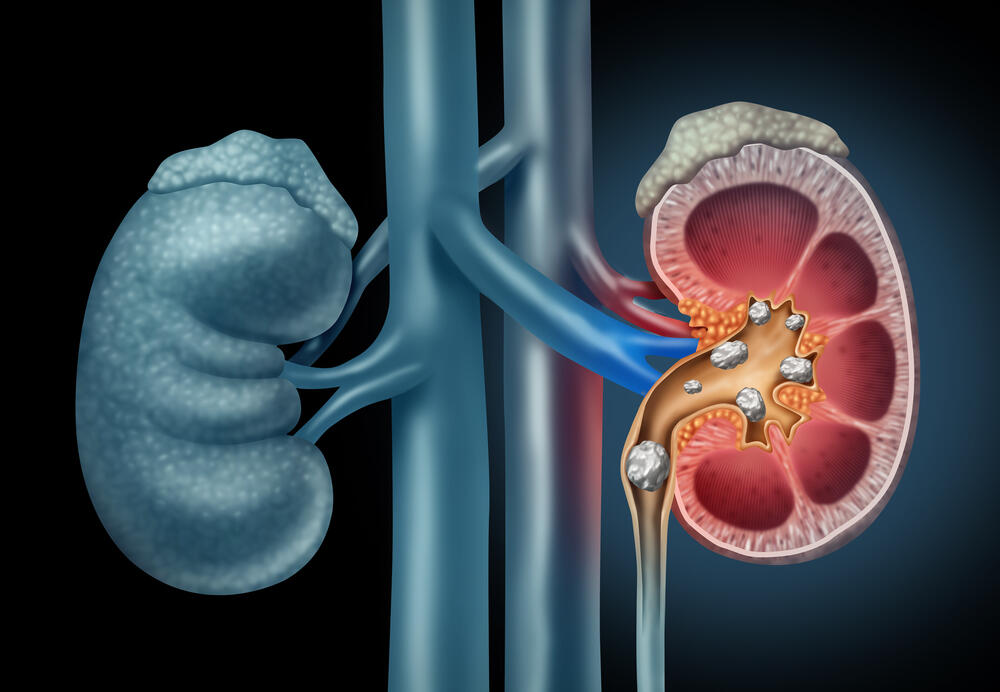

U bubrezima

Naslage kalcijuma u bubrezima prouzrokuju stanje koje se naziva nefrokalcinoza. To je relativno rijetko stanje koje obično pogađa oba bubrega istodobno. Tačan uzrok kalcifikacije bubrega nije poznat, ali pokazalo se da visok nivo kalcijuma u mokraći, što se naziva hiperkalciurija, može biti faktor rizika.

Postoji i vrsta bubrežnih kamenaca sačinjena od kalcijuma koji mogu izazvati vrlo neprijatne simptome, poput nepodnošljivog bola, povišene tjelesne temperature, a može se pojaviti i krv u mokraći, ali ponekad bubrežni kamenci ne moraju izazivati nikakve simptome.